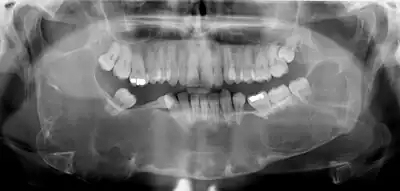

Classic look of an odontogenic keratocyst of the right mandible in the place of a former wisdom tooth. Well defined, unilocular, radiolucent lesion within the bone.

Diagnosis is usually radiological. However, definitive diagnosis is through biopsy. Aspirational biopsy of odontogenic keratocysts contains a greasy fluid which is pale in colour and contains keratotic squames.[12][2] Protein content of cyst fluid below 4g% is diagnostic of odontogenic keratocysts.[2] Smaller and unilocular lesions resembling other types of cysts may require a biopsy to confirm the diagnosis.[9] On a CT scan, the radiodensity of a keratocystic odontogenic tumour is about 30 Hounsfield units, which is about the same as ameloblastomas. However, ameloblastomas show more bone expansion and seldom show high density areas.[13]

Radiographs of odontogenic keratocysts show well-defined radiolucent areas with rounded or scalloped margins which are well demarcated.[12] These areas can be multilocular or unilocular. The growth pattern of the lesion is very characteristic from which a diagnosis can be made as there is growth and spread both forward and backward along the medullary cavity with little expansion. No resorption of teeth or inferior dental canal and minimal displacement of teeth is seen. Due to lack of expansion of the odontogenic keratocyst, the lesion can be very large when radiographically discovered.[9]